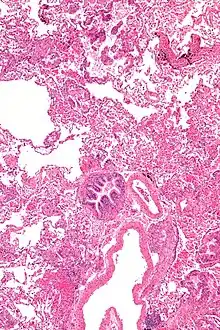

Micrograph of lymphangioleiomyomatosis. H&E stain

Grossly, LAM lungs are enlarged and diffusely cystic, with dilated air spaces as large as several centimeters in diameter.[105][106] Microscopic examination of the lung reveals foci of smooth muscle-like cell infiltration of the lung parenchyma, airways, lymphatics, and blood vessels associated with areas of thin-walled cystic change. LAM lesions often contain an abundance of lymphatic channels, forming an anastomosing meshwork of slit-like spaces lined by endothelial cells. LAM cells generally expand interstitial spaces without violating tissue planes but have been observed to invade the airways, the pulmonary artery, the diaphragm, aorta, and retroperitoneal fat, to destroy bronchial cartilage and arteriolar walls, and to occlude the lumen of pulmonary arterioles.[105]

There are two major cell morphologies in the LAM lesion: small spindle-shaped cells and cuboidal epithelioid cells.[107] LAM cells stain positively for smooth muscle actin, vimentin, desmin, and, often, estrogen and progesterone receptors. The cuboidal cells within LAM lesions also react with a monoclonal antibody called HMB-45, developed against the premelanosomal protein gp100, an enzyme in the melanogenesis pathway.[107] This immunohistochemical marker is very useful diagnostically, because other smooth muscle-predominant lesions in the lung do not react with the antibody.[108] The spindle-shaped cells of the LAM lesion are more frequently proliferating cell nuclear antigen positive than the cuboidal cells, consistent with a proliferative phenotype.[107] Compared with cigar-shaped normal smooth muscle cells, spindle-shaped LAM cells contain less abundant cytoplasm and are less eosinophilic. Estrogen and progesterone receptors are also present in LAM lesions,[109][110][111] but not in adjacent normal lung tissue.[112] LAM lesions express lymphatic markers LYVE-1, PROX1, podoplanin and VEGFR-3. The smooth muscle-like cells of AMLs are morphologically and immunohistochemically similar to LAM cells, including reactivity with antibodies directed against actin, desmin, vimentin, and HMB-45 as well as estrogen and progesterone receptors.[113][114] Unlike the dilated airspaces in emphysema, the cystic spaces found in LAM may be partially lined with hyperplastic type II cells.[115]